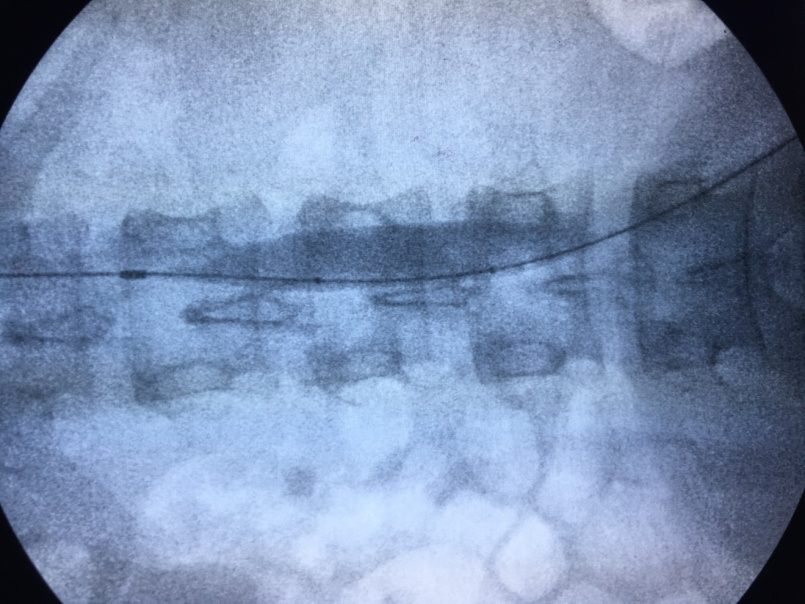

这次也不例外,如此高危的患者,第一时间就联系到血管外科,崔文军主任高度重视,考虑到患者的特殊情况,与我院血管外科首席专家王兵教授一起拟定手术方案。付建红主任建议先由血管外科在局麻下植入阻断球囊,然后再全麻完成剖宫产,这样可以缩减全麻时间,减少风险。时间就是生命,很快在崔文军主任指示下,短短几分钟时间司江涛及王颖医师就在局麻下植入用于阻断的球囊,一切准备就绪,剖宫产手术由经验丰富的李巧云主任,付建红主任共同完成。10分钟不到就顺利娩出胎儿,大出血往往在剥离胎盘时,此时大家精神高度集中,待胎盘成功剥离,司江涛医生迅速充填位于腹主动脉下段的预置球囊,阻断腹主动脉(下图),子宫出血明显减少,此时李主任团队非常顺利的完成了创面的止血,阻断时间约15分钟,术中失血约1500ml,要知道平时这样的患者平均失血量在4000-5000ml!一个简单的小技术既减少了产妇术中出血,又尽可能保住了患者的子宫,技术的进步创造了无限可能,学科的合作让可能变为可以。

▲ 术中腹主动脉球囊阻断

什么样是手术竟然可以让“凶险的前置胎盘”变得不再凶险。简单地说,腹主动脉球囊阻断术就是在数字血管造影机的(DSA)引导下,将球囊放置在腹主动脉里,孕妇分娩过程中一旦出现大出血,立即扩张球囊,堵住血管,阻断血供,大大降低术中出血风险。